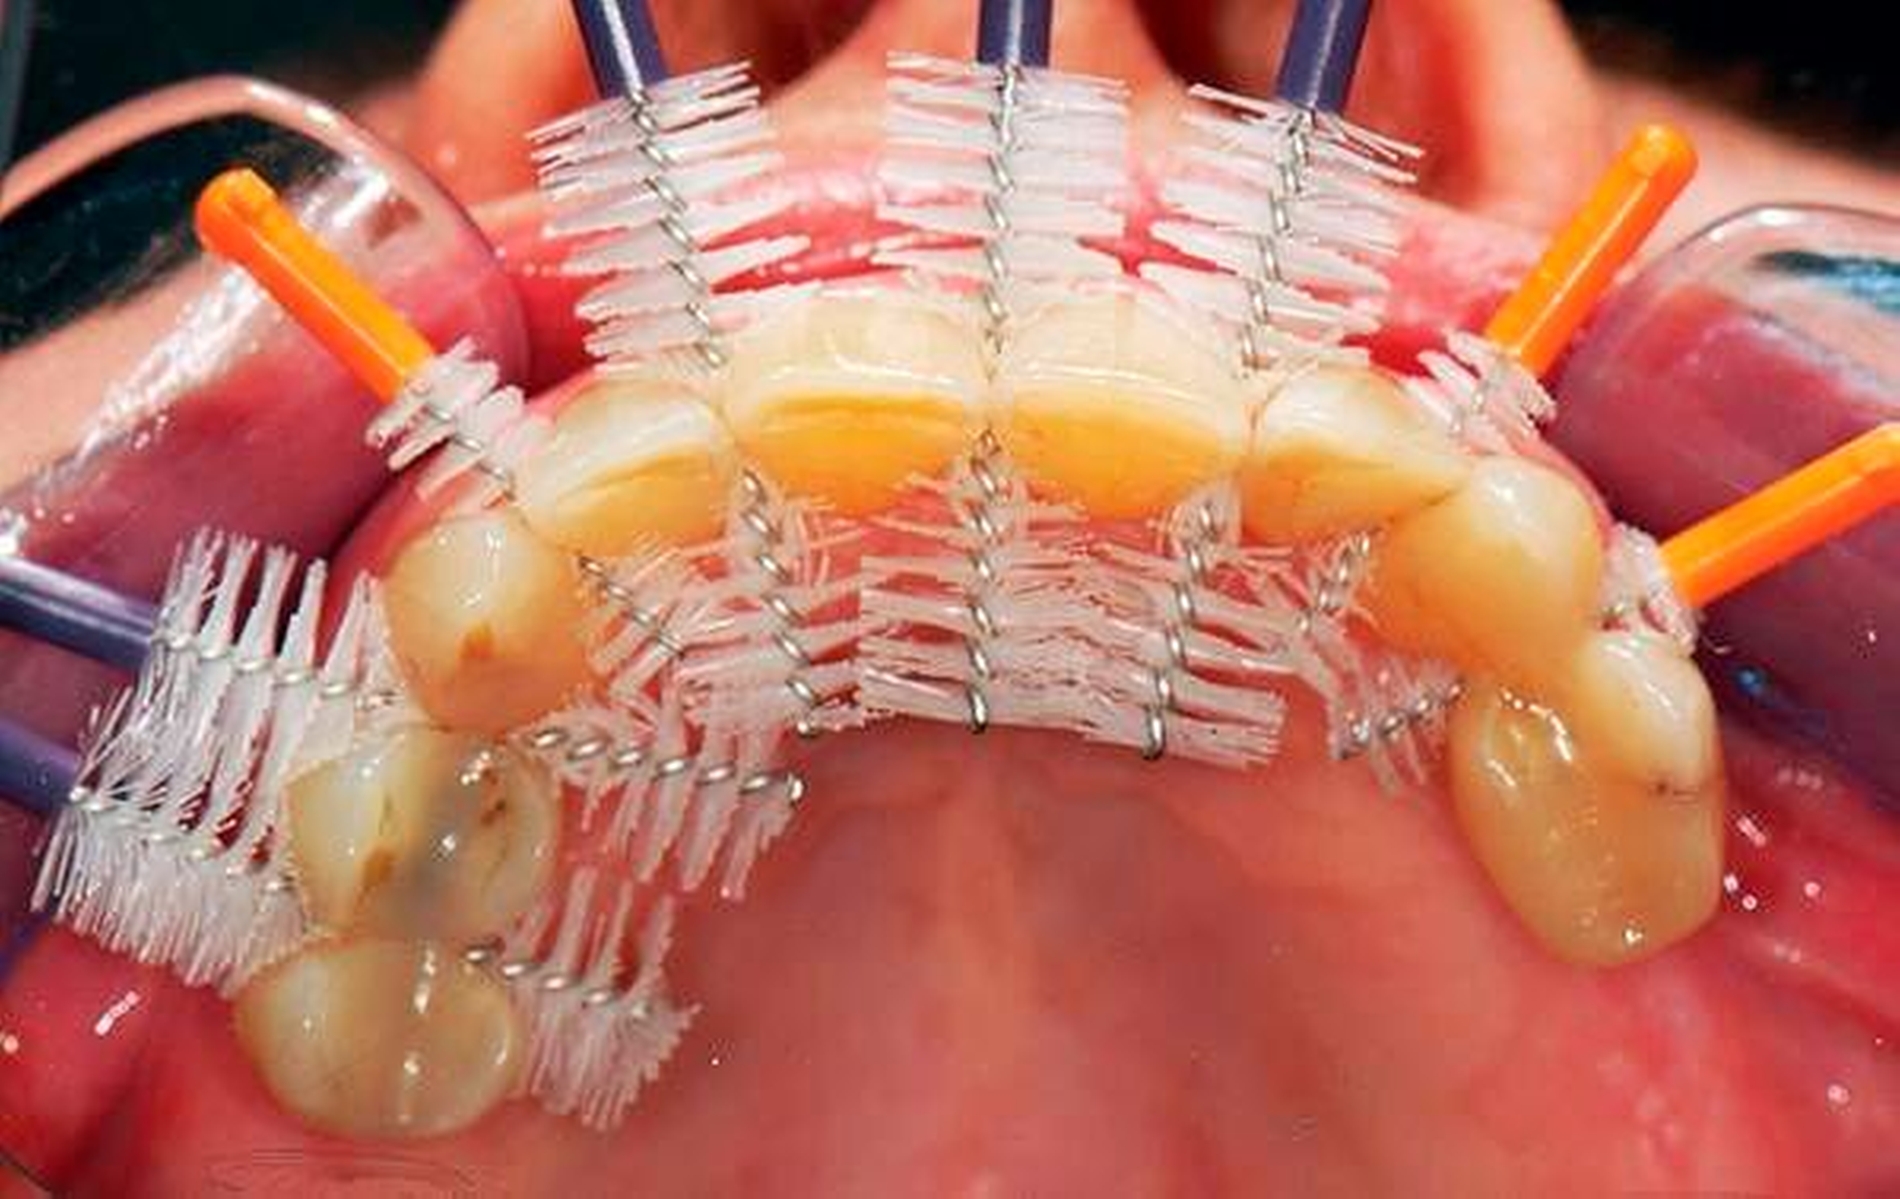

Wenn beispielsweise ein Patient mit tiefen Zahnfleischtaschen Interdentalraumbürsten anwendet, die ohne nennenswerten Widerstand die Zahnzwischenräume passieren, kann man nicht erwarten, dass ihm dies zu einem großen Nutzen für die Zahngesundheit verhilft. Dies betrifft auch Implantatträger [Staehle et al., 2016]. In Abbildung 7 ist ein Patient gezeigt, der trotz Parodontalbehandlung und regelmäßiger Reinigung mit einer – zu dünnen – Interdentalraumbürste hohe Sondierungstiefen und Bluten nach Sondieren aufwies. Erst nach Umstellung auf eine größere Interdentalraumbürste mit längeren Seitenborsten und einem genügend hohen Passagewiderstand durch den Interdentalraum wurde der Taschenfundus mit den Borsten besser erreicht und es kam zu einem deutlichen Entzündungsrückgang.

Eine zahnmedizinisch sinnvolle frugale Intervention für viele Menschen wäre, ihnen eine Handzahnbürste zu empfehlen und dies bedarfsgerecht durch geeignete Interdentalraumbürsten zu ergänzen. Dies wäre in manchen Fällen wesentlich besser, als jemanden durch die alleinige Empfehlung einer elektrischen Hightech-Zahnbürste in einer falschen Sicherheit zu belassen und auf Interdentalraumbürsten zu verzichten. Allerdings muss man einräumen, dass derzeit Interdentalraumbürsten relativ teuer und verschleißanfällig sind und dass das oft sehr unübersichtliche und unvollständige Produktangebot nicht den tatsächlichen Erfordernissen genügt. Insofern besteht hier auch von Herstellerseite Handlungsbedarf.